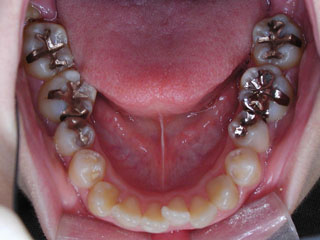

主訴:上顎前歯の突出 口が閉じにくい

診断名:叢生と伴う上顎前突

年齢:13歳

使用した主な装置名:TPB、HG、マルチブラケット装置

抜歯/非抜歯および抜歯部位:抜歯(上顎左右第一小臼歯)

治療期間:動的処置2年6か月、経過観察3年6ヶ月

上顎前歯の前突が見られます。下の歯には中程度の叢生と口唇前突感がみられました。分析結果では、2級1類と呼ばれるタイプの不正咬合でした。上顎の左右第一小臼歯を抜歯してマルチブラケット治療を行いました。